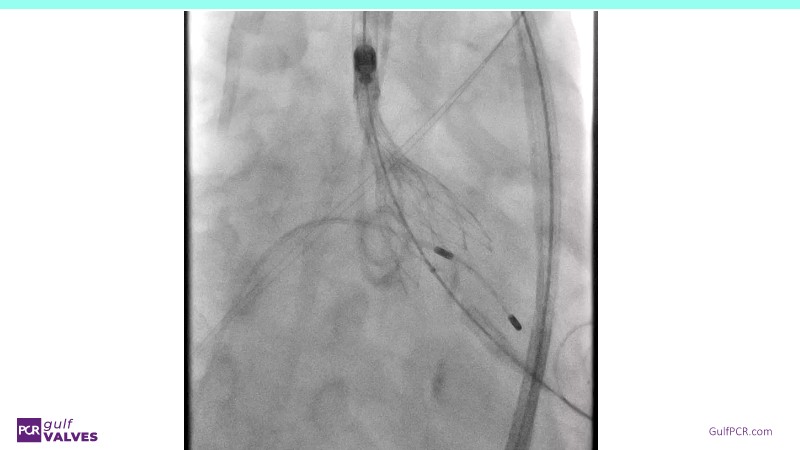

Discover a selection of cases showcasing the key features of the Navitor Valve System and its clinical applications. This session explores auxiliary access, the use of Navitor in alternative access and complex PCI, its performance in challenging peripheral anatomies, and innovative outcomes with the Vantage 30D system.